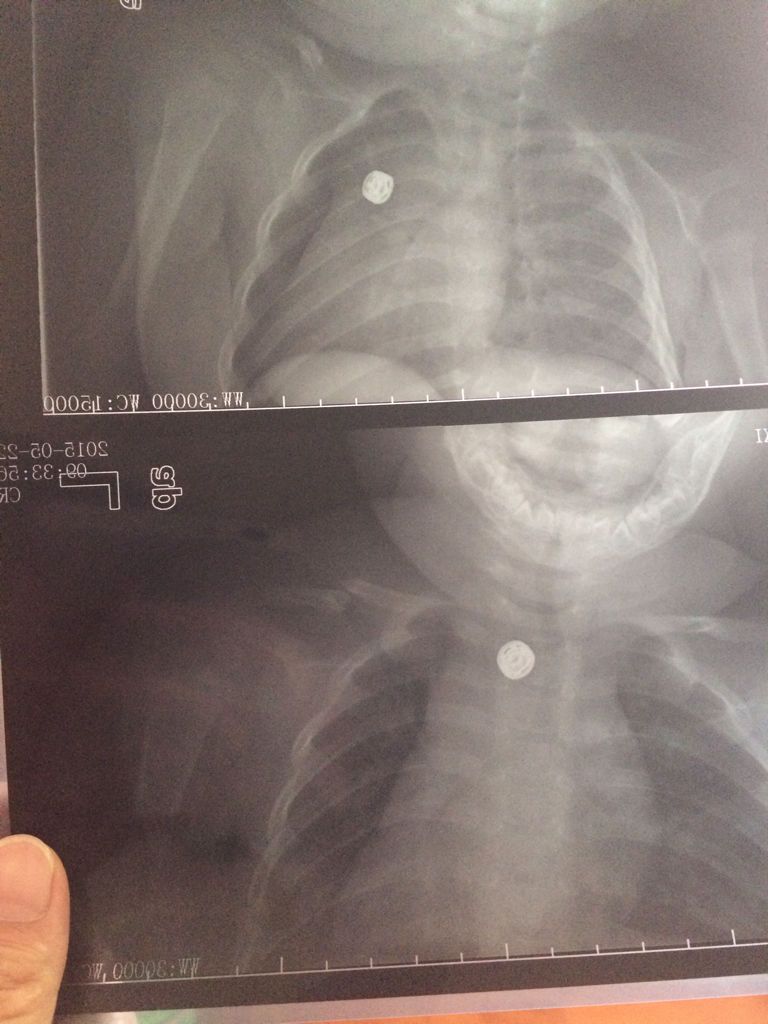

6个月宝宝左锁骨骨折,缠了八字绷带第二天左脸肿了怎么办 点击展开 匿名用户 2015-05-23 11:41 为您推荐: 其他回答 脸肿是因为绑得太紧,头面部的静脉回流不好导致的,建议到医院调整绑带的松紧度 笑天下美女 2015-05-23 12:43 相关问题 6个月宝宝从床上摔地上了,左侧朝下,左锁骨骨折了,医生缠了绷带,第二天左脸上 新生儿锁骨骨折错位了,当时拍片是发现,后来医生接了,还打了绷带,现在已经两周了,到医院复查后发现断 你好,我家宝宝17个月大了,锁骨骨折给她绑了8字绷带,绑了